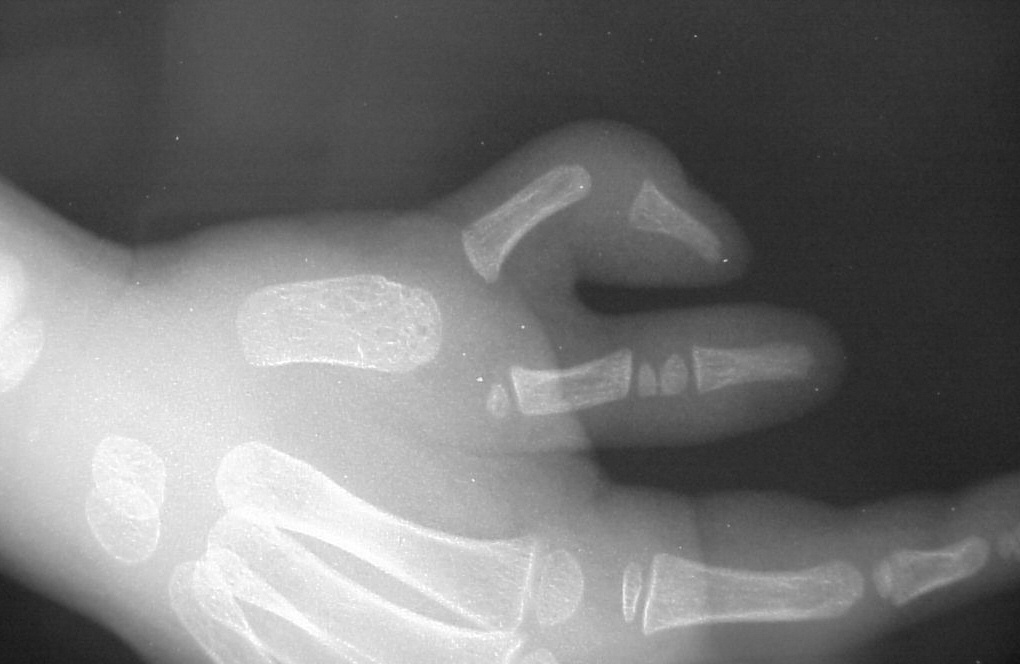

| Case 1. Wassell IV duplication of the proximal and distal phalanges, with characteristic deviation of the thumbs away from each other at the MCP and toward each other at the IP joints. This was corrected by metacarpal head narrowing, opposing closing wedge osteotomies of the metacarpal and proximal phalanx and collateral ligament reconstruction using parts from the deleted digit. |